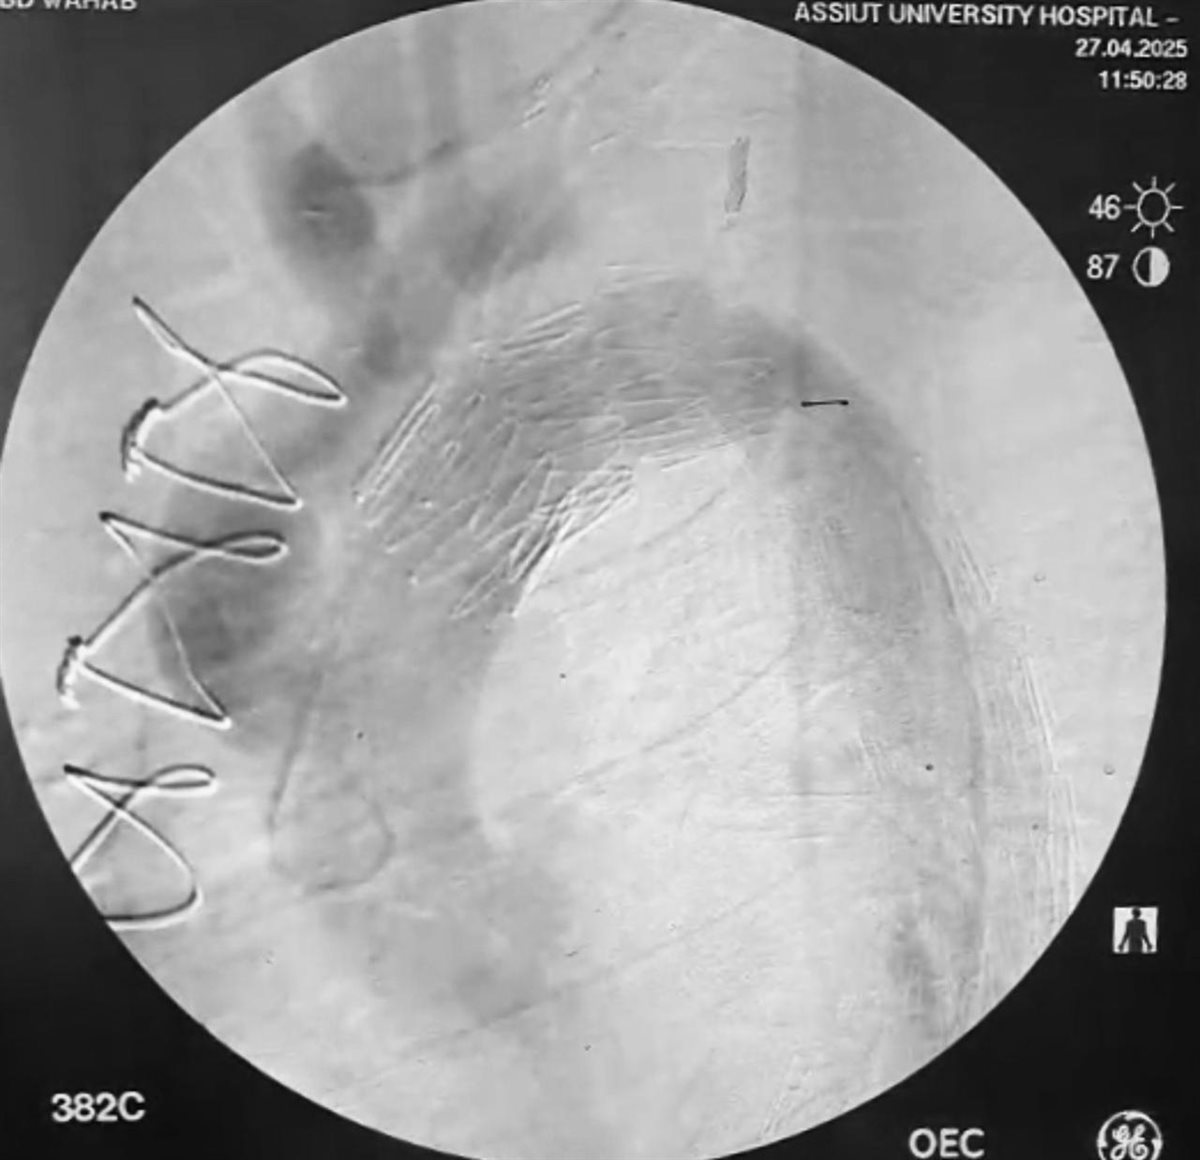

بينما تضمنت المرحلة الثانية استخدام القسطرة التداخلية بعد تخطيط دقيق وتنسيق وثيق بين التخصصات المختلفة، حيث قام الفريق الطبي بقسم جراحة الأوعية الدموية بالمستشفى الجامعى الرئيسى تحت إشراف الدكتور خالد عبد العزيز مدير المستشفى، وبرئاسة الدكتور هيثم علي حسن رئيس القسم، وضم كلا من: الدكتور محمود إسماعيل، أستاذ جراحة الأوعية الدموية، والطبيب أحمد نجيب، مدرس مساعد بالقسم، بإجراء إصلاح للانشطار بالشريان الأورطي الصدري والبطني باستخدام القسطرة التداخلية وتركيب دعامات مغطاة باستخدام تقنية (TEVAR).

وعقب ذلك قامت الدكتورة سلمى طه، أستاذ مساعد بقسم القلب، باستخدام تقنية التحفيز البطيني السريع من خلال تركيب منظم ضربات قلب مؤقت بالبطين الأيمن، والذى ساهم في تقليل حركة جدار الشريان الأورطي لزرع الدعامة المغطاة بالشريان الأورطي بدقة.